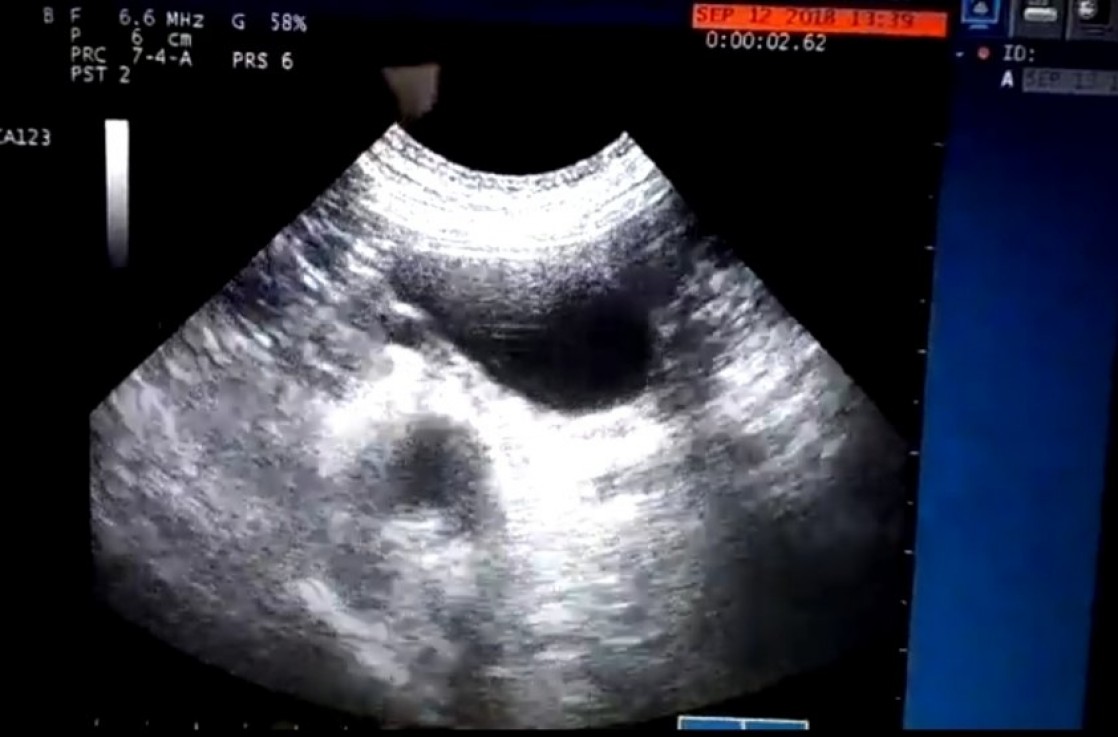

Para comprobarlo, en eco realizamos una tecnica llamada ''inyeccion intravesical de suero salino agitado'' que consiste en introducir suero agitado con burbujas de aire a traves de la sonda urinaria. Gracias a este aire introducido podemos ver en que direccion se van las burbujas de aire, si se quedan dentro de la vejiga o salen al abdomen, en este caso comprobamos que las burbujas se escapaban a la cavidad abdominal por la parte caudal de la vejiga, es decir, la vejiga estaba rota.